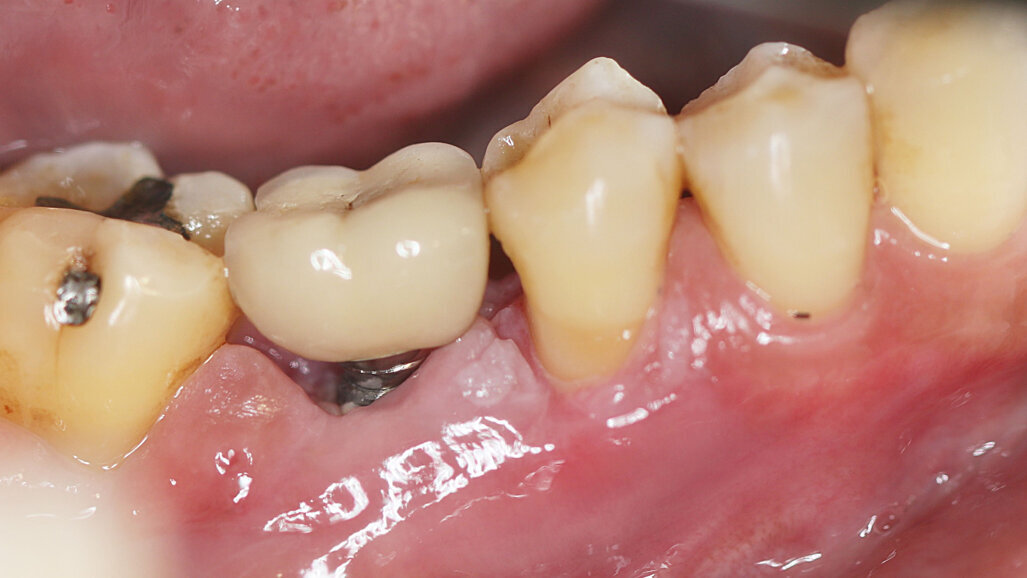

MADRID, Spain: The global dental implant market was worth US$4.6 billion (€4.2 billion) in 2022 and is expected to grow annually by 10% until 2030, according to market analysis. Considering that recent research indicates that the rates of peri-implantitis exceed 19%, clinicians have valid reason to be concerned with its prevention. The European Federation of Periodontology (EFP) has therefore published the highest-quality level (S3) clinical practice guideline for the prevention and treatment of peri-implant mucositis and peri-implantitis. The guideline promotes an interdisciplinary approach and is targeted at oral health clinicians, health systems decision makers, other medical professionals and the public.

According to the guideline, clinicians should be strategising prevention from the moment the decision to pursue implant treatment has been made. Utilising a patient-centred and evidence-based decision-making process, the new guideline outlines specific interventions that can be undertaken for both prevention and treatment of peri-implant disease. The guideline also offers a handy evaluation of the available scientific information for a number of popular implant processes and methods. These evidence-based recommendations are provided with the aim of helping clinicians maintain the health of peri-implant tissue and increase implant longevity.